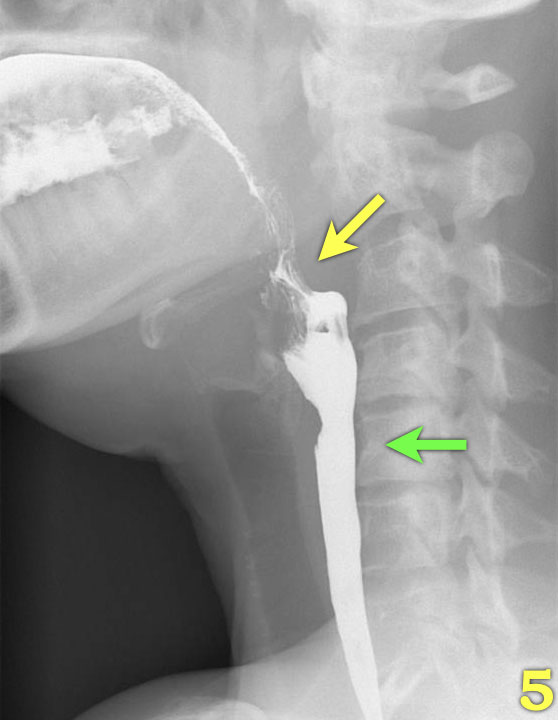

Các hình ảnh quan trọng nhất trong nghiên cứu nuốt là những hình ảnh chụp ở tư thế nghiêng (lateral view).

Nhấp qua các hình ảnh 1-7 ở bên trái.

- Nền lưỡi và vòm miệng mềm đóng khoang miệng ở phía sau (mũi tên) để ngăn thức ăn tràn vào hầu họng và thanh quản đang mở.

- Lưỡi bắt đầu vận chuyển thức ăn về phía hầu họng (mũi tên vàng).

Thanh quản vẫn còn mở và ở vị trí bình thường (mũi tên xanh lá). - Vòm miệng mềm nâng lên để ngăn thức ăn tràn vào vòm mũi họng (mũi tên xanh lá) và lưỡi đẩy thức ăn tiếp tục ra phía sau (mũi tên vàng).

- Xương móng nâng lên và thanh quản đóng lại (mũi tên xanh lá). Lưỡi đẩy thức ăn xuống dưới trong khi cơ khít thực quản trên co lại.

- Sự co thắt của cơ khít hầu giữa (mũi tên vàng), trong khi cơ nhẫn hầu đã giãn hoàn toàn (mũi tên xanh lá).

- Sự co thắt của cơ khít hầu dưới làm tống xuất hầu họng.

- Nắp thanh thiệt nâng lên để trở về vị trí nghỉ và thanh quản mở ra (mũi tên).